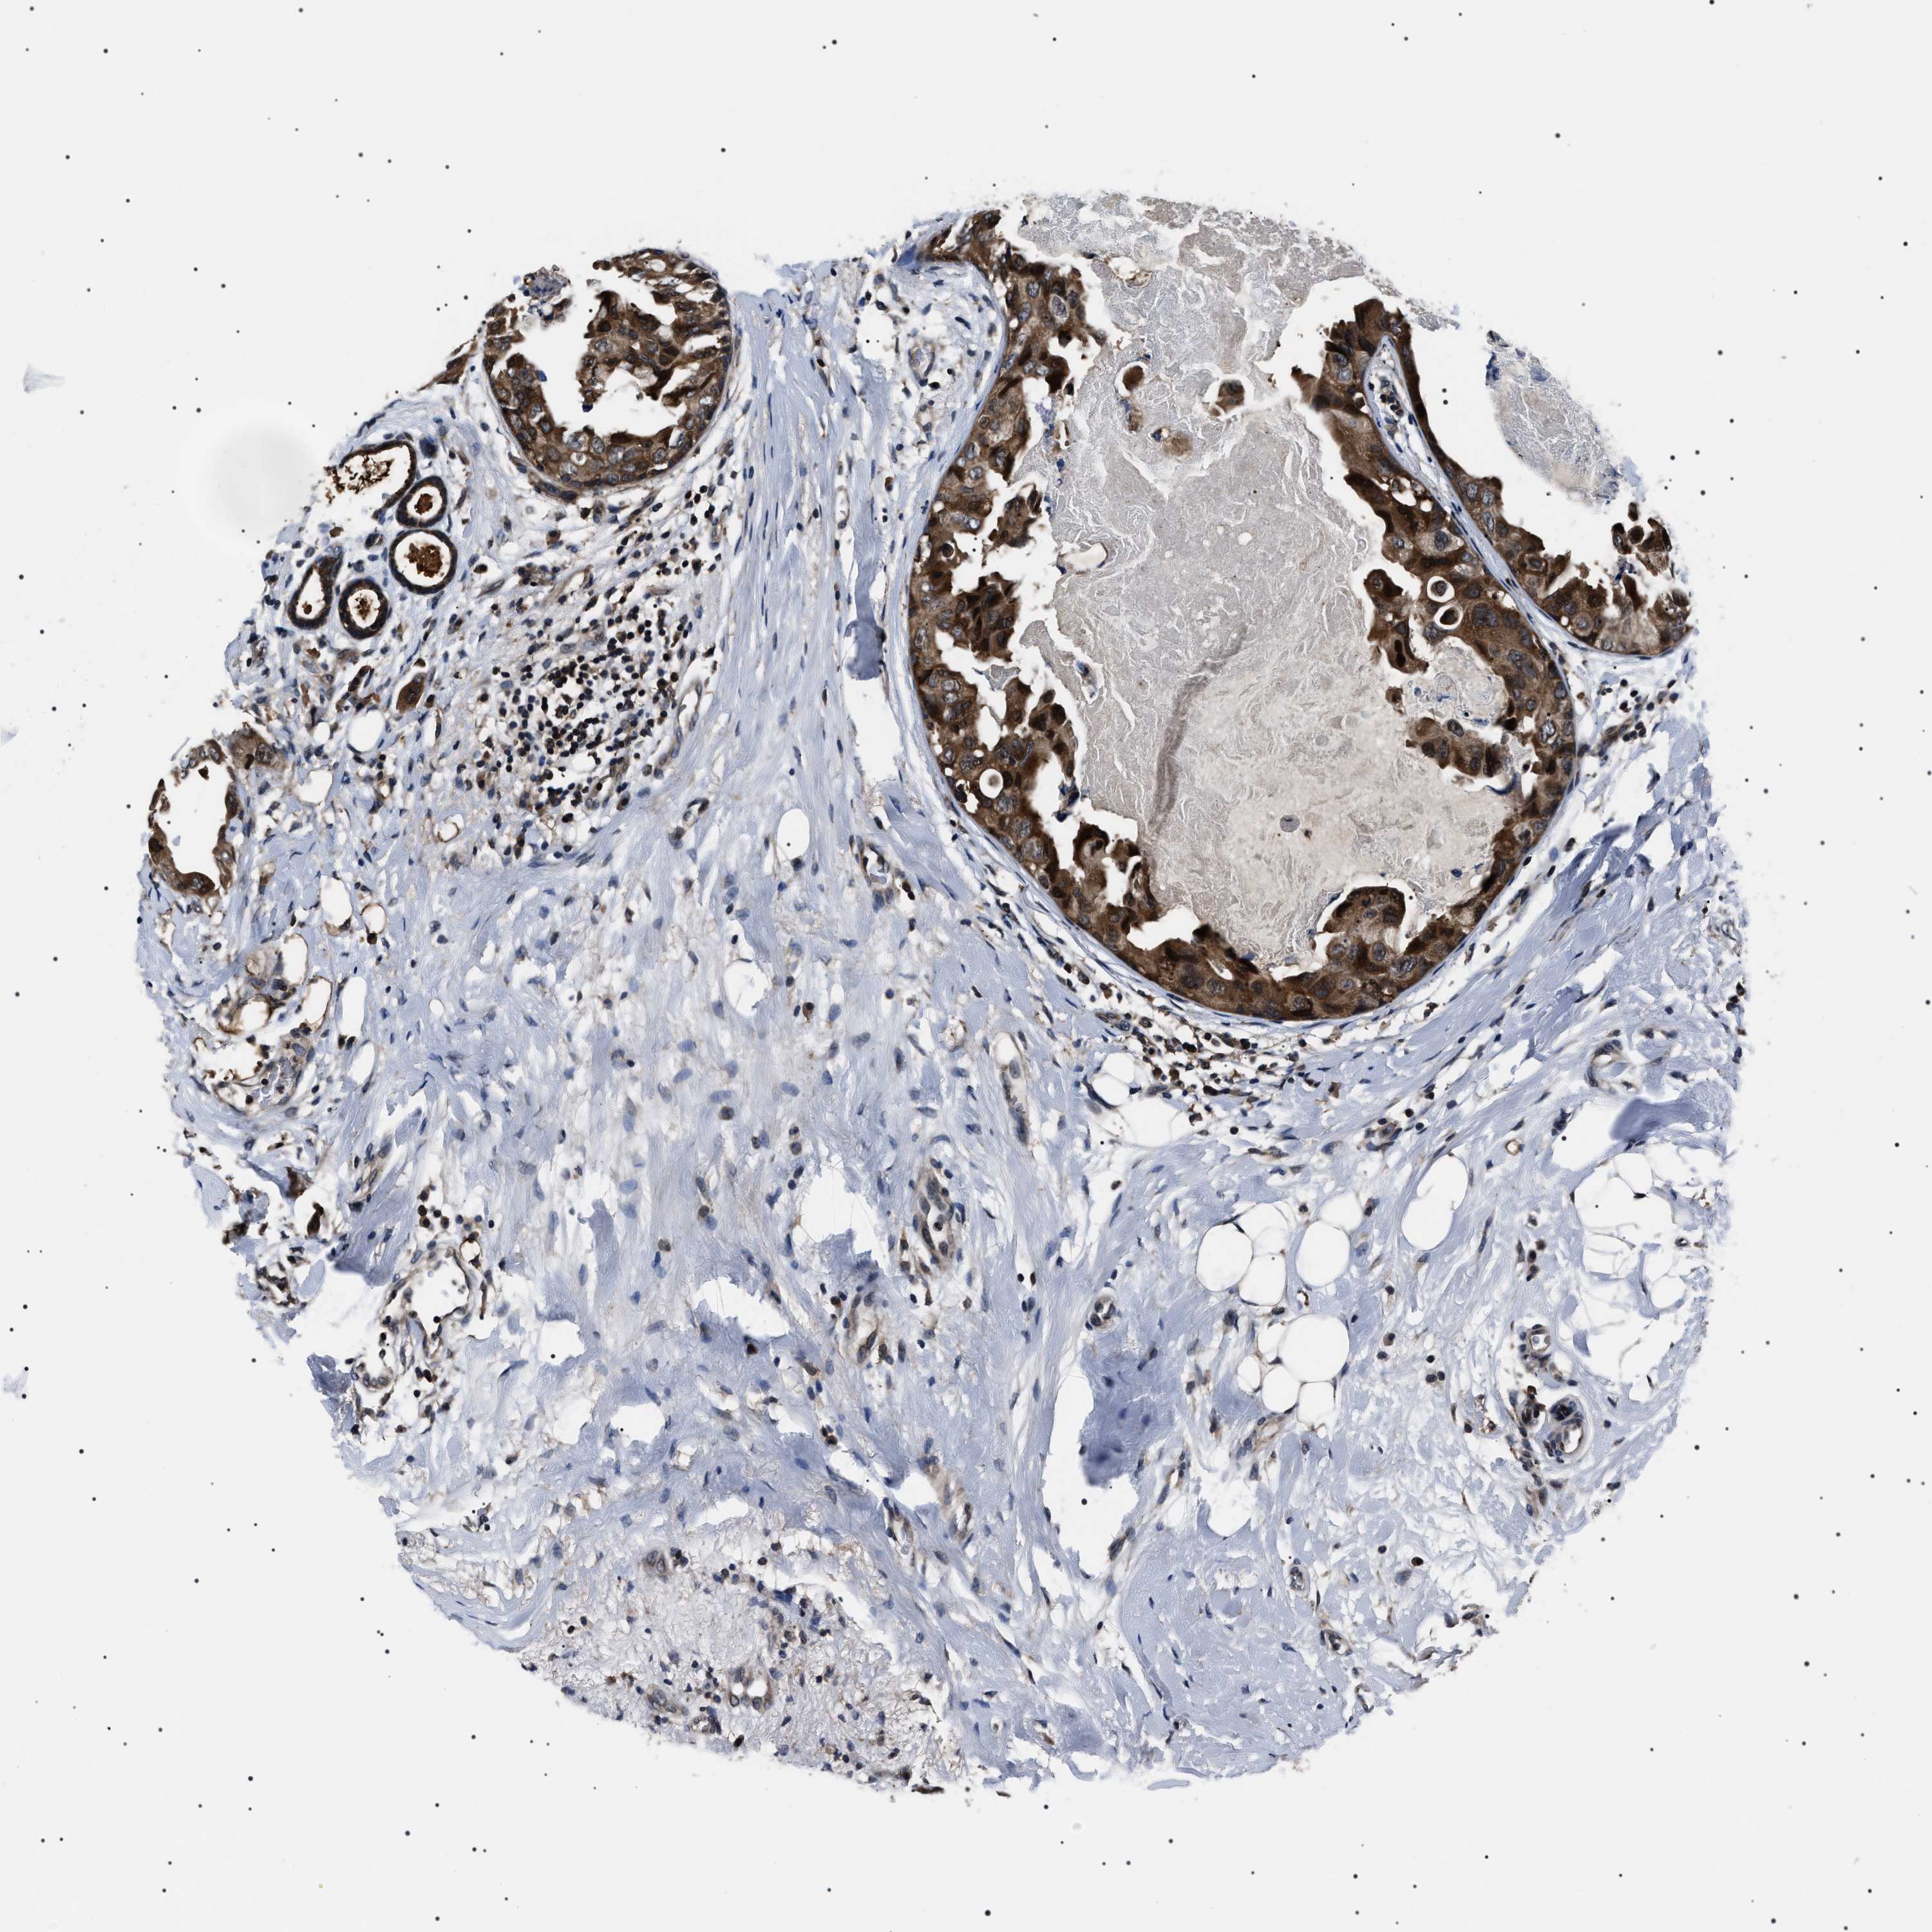

CANCER BREAST CANCER Show tissue menu

BRCA TCGA BRCA VALIDATION PROTEIN EXPRESSION